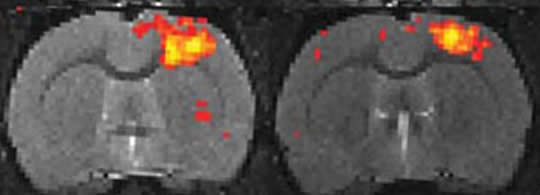

The researchers, led by Jin Hyung Lee of the Department of Electrical Engineering, Psychiatry and Biobehavioral Sciences at the University of California, Los Angeles, and Remy Durand of the Department of Bioengineering at Stanford University, were able to show specific target neurons “light up” on the fMRI scans when they activated them with light pulses.

The researchers used an approach called optogenetics, in which genetically engineered neurons are controlled by light pulses, in mice under general anesthesia. And when the team manually activated particular brain cells with the pulses, those areas flashed on the fMRI screen as well, which suggests that the blood flow changes seen in fMRIs do seem to be evidence for neuron activity in that location. [From ScientificAmerican.com – New evidence that fMRI experiments are valid measure of neuron activity by Katherine Harmon.]

In one experiment, for example, the team could see how activity they stimulated in the thalamus, a key relay center deep in the brain, could affect circuits stretching into the somatosensory cortex, a surface brain region important in processing sensation.